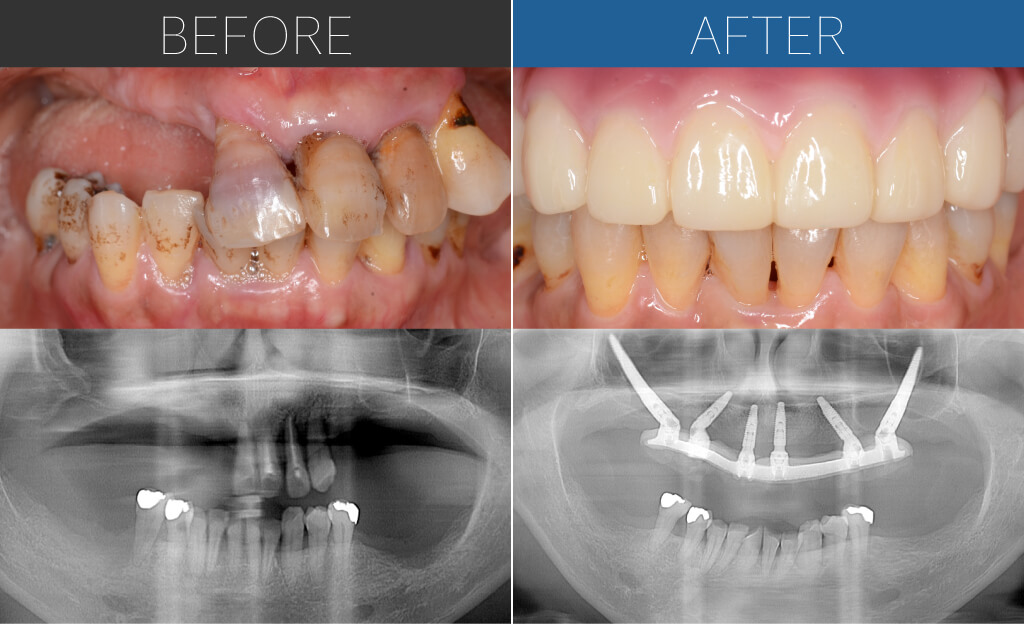

– Upper:All-on-4 + Zygoma

– Lower:All-on-4

Age:60s

| 治療内容 | 差し歯が合わなくなってきて、歯茎に痛みを感じて来院。重度歯周病のため、上顎は通常の埋入が難しくザイゴマインプラント。下顎は基本的な4本埋入によるオールオン4。上下ともに即時荷重により手術当日に仮歯を固定。 |